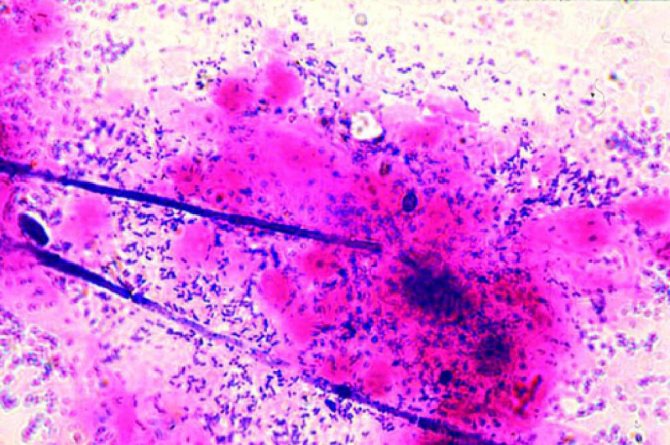

выделения из влагалища пахнут луком

почему выделения пахнут луком у женщины